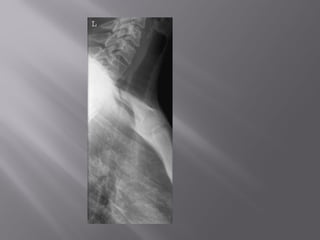

 Antero-posterior radiograph of trachea showing paratracheal

lymph node mass.

 Antero-posterior radiographof trachea showing paratracheal lymph node mass.

• 51.

 The patientstands or sits with either shoulder against a vertical Bucky.  The median sagittal plane of the trunk and head are parallel to the cassette.  The cassette should be large enough to include from the lower pharynx to the lower end of the trachea at the level of the sternal angle.  The shoulders are pulled well backwards to enable the visualization of the trachea.  This position is aided by the patient clasping their hands behind the back and pulling their arms backwards.  The cassette is centred at the level of the sternal notch.